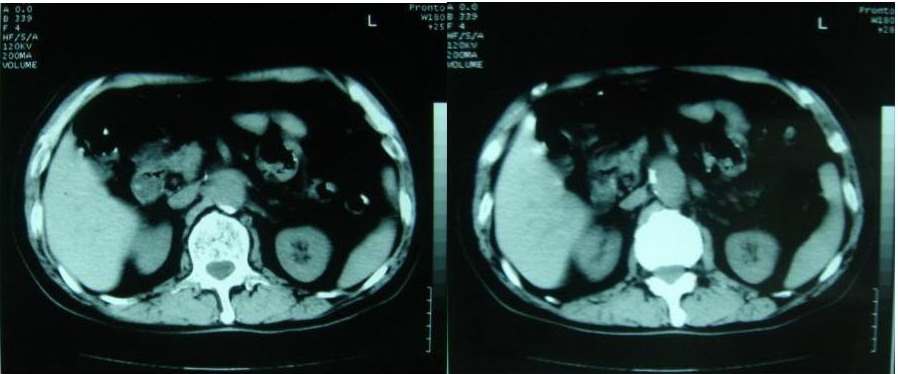

以下是引用zjzjr在2007-8-29 17:09:00的发言:[br]典型腹主动脉瘤累及双侧髂总动脉,建议增强扫描.

以下是引用why7912在2007-8-29 19:08:00的发言:[br]典型夹层动脉瘤,可见真假双腔及附壁血栓

以下是引用借我一双慧眼在2007-8-29 16:24:00的发言:[br]典型腹主动脉瘤累及双侧髂总动脉

以下是引用快乐男生在2007-8-29 16:45:00的发言:[br]腹主动脉及右髂总动脉大范围的管径增粗,[br]管壁多发的钙化,[br]并见真假腔(双腔征),假腔可见附壁血栓.[br]考虑腹主动脉夹层动脉瘤 .建议增强或mri